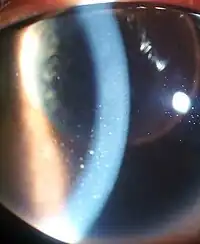

| Inflammation of the eye and keratic precipitates due to uveitis | |

Uveitis (/ˌjuːvi.aɪtɪs/) is inflammation of the uvea, the pigmented layer of the eye between the inner retina and the outer fibrous layer composed of the sclera and cornea.[1] The uvea consists of the middle layer of pigmented vascular structures of the eye and includes the iris, ciliary body, and choroid. Uveitis is described anatomically, by the part of the eye affected, as anterior, intermediate or posterior, or panuveitic if all parts are involved. Anterior uveitis (iridocyclitis) is the most common, with the incidence of uveitis overall affecting approximately 1:4500, most commonly those between the ages of 20-60. Symptoms include eye pain, eye redness, floaters and blurred vision, and ophthalmic examination may show dilated ciliary blood vessels and the presence of cells in the anterior chamber. Uveitis may arise spontaneously, have a genetic component, or be associated with an autoimmune disease or infection. While the eye is a relatively protected environment, its immune mechanisms may be overcome resulting in inflammation and tissue destruction associated with T-cell activation.

- Signs of anterior uveitis include dilated ciliary vessels, presence of cells and flare in the anterior chamber, and keratic precipitates ("KP") on the posterior surface of the cornea. In severe inflammation there may be evidence of a hypopyon. Old episodes of uveitis are identified by pigment deposits on lens, KPs, and festooned pupil on dilation of pupil.